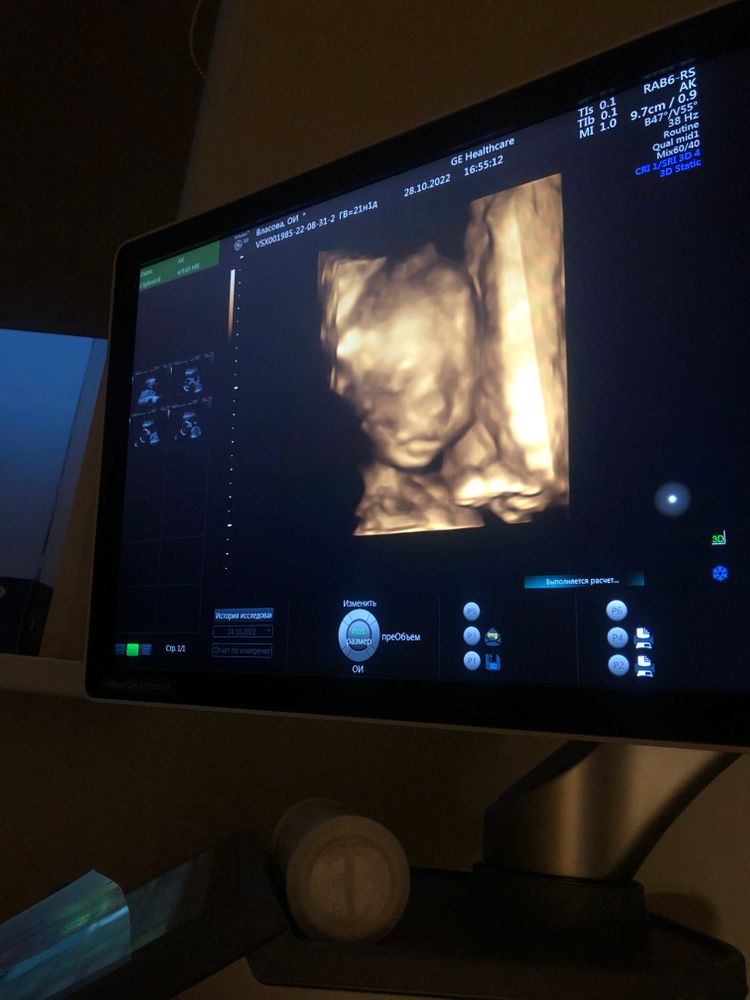

В этот раз показал нам личико, сделали даже 3Д фото. Такие мы уже большие😍 мальчишки с пухлыми губами😁 (срок 20 недель и 1 день, по узи 21 неделя и 1 день)

Губы у малыша папины, пухлые😁 А вот нос картошка похоже, это мой🤣